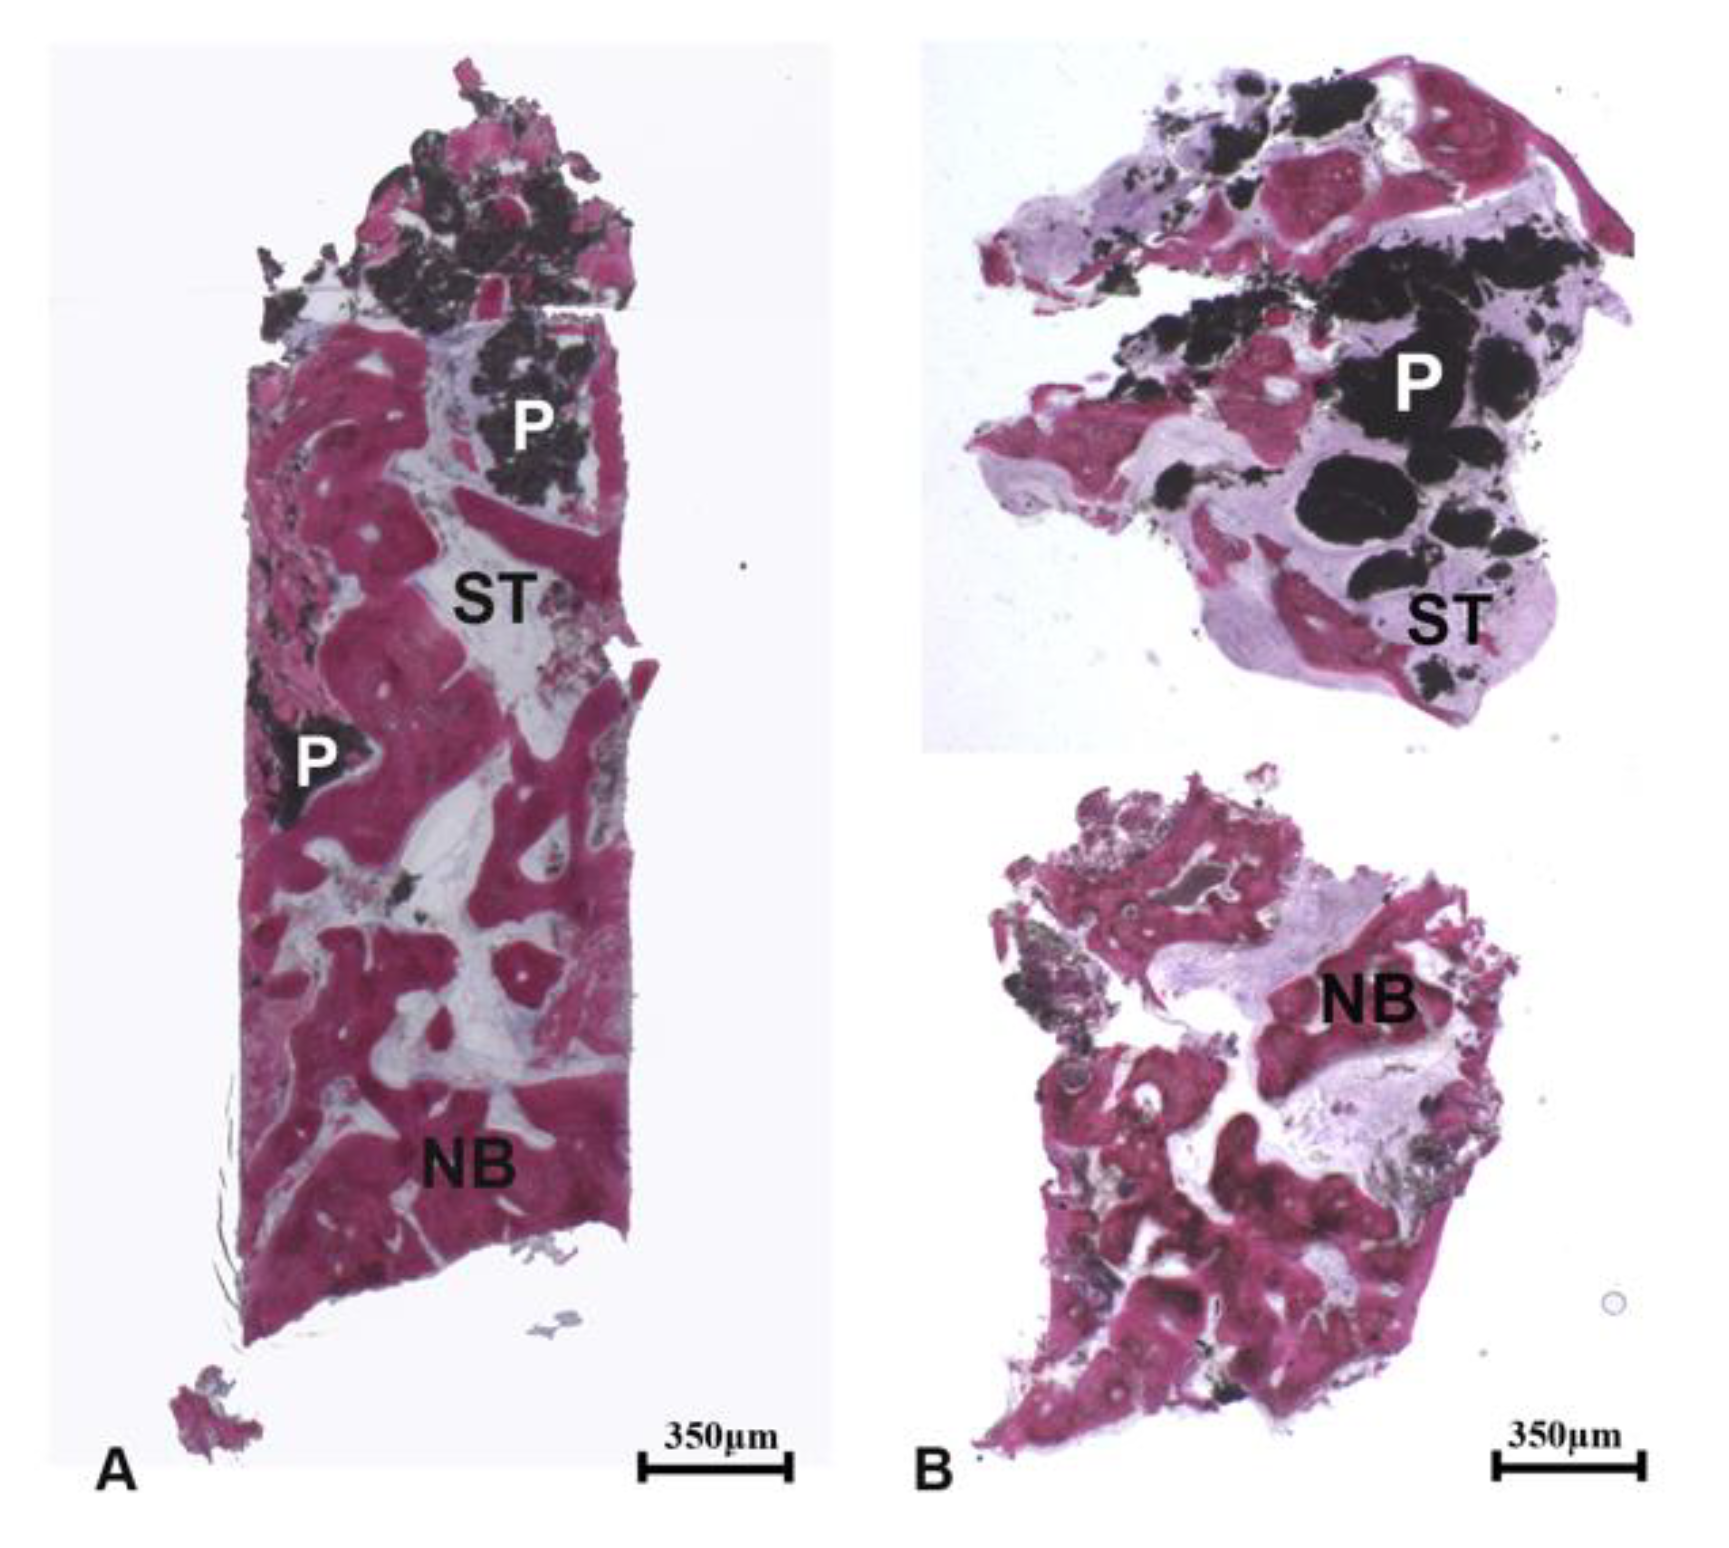

In the coronal portion of the biopsies (occlusal region), the regenerated area consisted of newly formed trabecular bone, soft tissues, and residual biomaterial particles which were partially surrounded by new bone (

Figure 3a). The connective tissue adjacent to the newly formed bone was well vascularized; thus, it could be hypothesized that this tissue plays a crucial role in the vascularization of the newly augmented bone. The surface of residual biomaterial particles showed signs of degradation. Some lymphocytes and many blood vessels were present close to them (

Figure 3b).

At low magnification, the samples presented newly formed trabecular bone, soft tissues, and residual biomaterial particles (

Figure 4a,b).